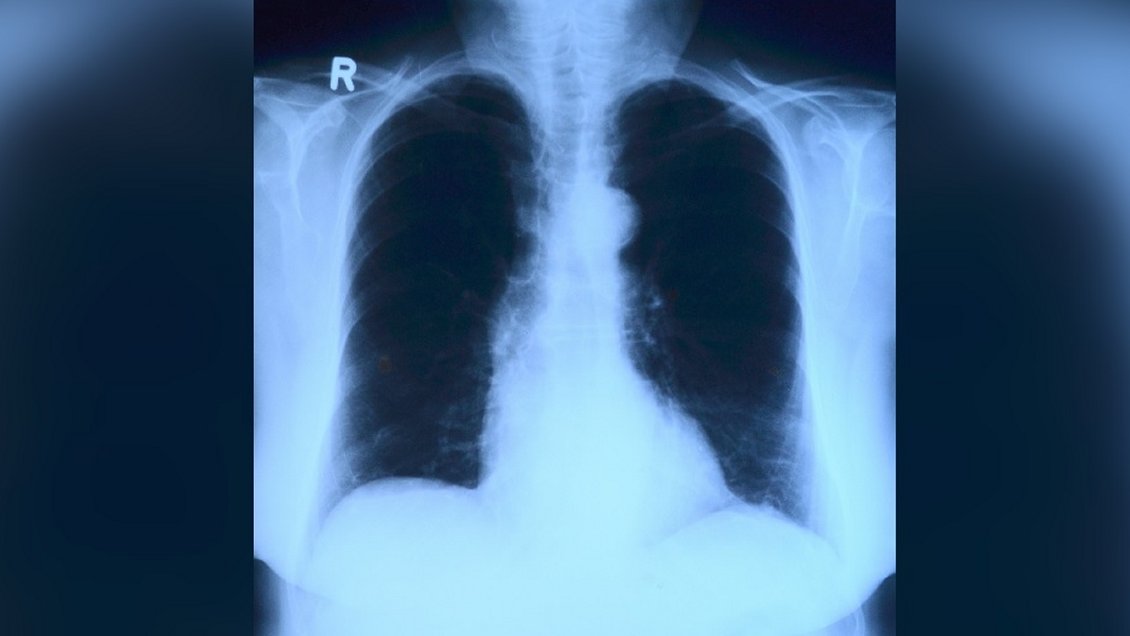

El estudio demuestra que las imágenes de rayos X combinadas con técnicas de inteligencia artificial son una alternativa eficaz para diagnosticar Covid-19, explicó la Universidad Católica de Valparaíso.

Una investigación liderada por el Centro de Data Science de la Escuela de Ingeniería Industrial de la Pontificia Universidad Católica de Valparaíso demostró que el machine learning (herramienta de inteligencia artificial de aprendizaje automático) aplicado a radiografías de tórax es capaz de diagnosticar con certeza el Covid-19.

El estudio, desarrollado junto a la Clínica MEDS (Sports Medicine Data Science Center MEDS-PUCV) evaluó las capacidades de las técnicas de aprendizaje automático para diagnosticar, mediante análisis computarizado, casos de coronavirus a partir de imágenes de rayos X.

Según señala en sus conclusiones -que fueron publicadas en la revista científica Signa Vitae, perteneciente al ISI web of Science (ver archivo adjunto)- esta técnica es capaz de diferenciar entre pacientes con Covid-19, personas sanas y pacientes con neumonía con una alta precisión (hasta un 90 por ciento), a bajo costo, y con infraestructura computacional sencilla y básica, lo que podría impactar positivamente en sectores donde no existe acceso ni infraestructura para el diagnóstico con PCR.

Mediante un comunicado, la casa de estudios explicó que la investigación se basó en radiografías de tórax de personas de 26 países, disponibles en un repositorio público de datos.

Incluyó un experimento estadístico diseñado para verificar si herramientas de aprendizaje automático, como máquinas de soporte vectorial y bosques aleatorios, detectaban pacientes Covid-19 positivos entre diferentes imágenes de rayos X de pacientes sanos, con neumonía y con coronavirus. "¿El resultado? Hasta un 90 por ciento de sensibilidad y especificidad en el diagnóstico", destacó a PUCV.

Al procesar radiografías de tórax, el machine learning es capaz de detectar con alta precisión qué pacientes presentan Covid-19 y cuáles no.